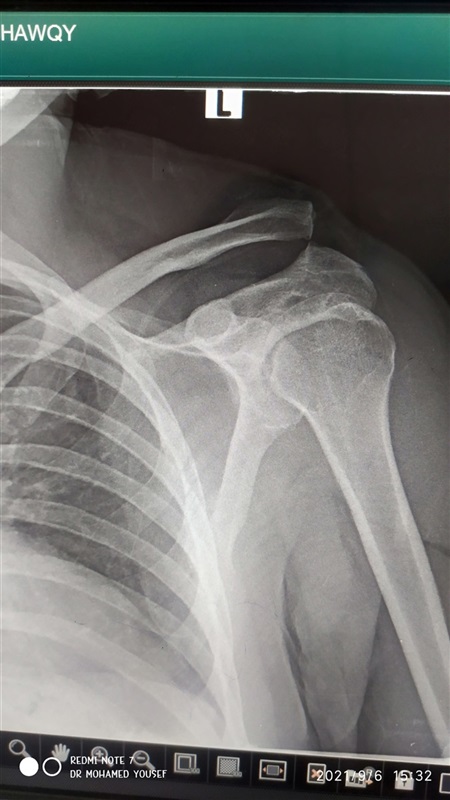

نجاح اول عملية تثبيت خلع بمفصل الكتف بتقنية جديدة بمستشفى دكرنس العام

اعلن الدكتور سعد مكي وكيل وزارة الصحة بالدقهلية عن نجاح فريق طبي بإجراء اول عملية تثبيت خلع بمفصل الكتف بتقنية جديده بمستشفى دكرنس العام لمريض يبلغ من العمر 40 عاما.

وأكد مكي ان استخدام التقنية الجديده، تقلل من آلام ما بعد الجراحة لدى المريض، وتحقق التعافي السريع وهي أفضل من الناحية التجميلية، كما أنها لا تستدعي إجراء عملية أخرى لإزالة الشرائح والمسامير المعدنيه.